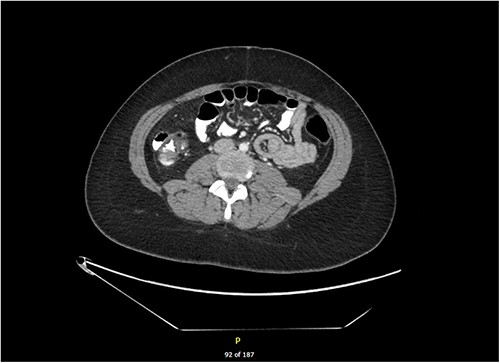

She was taken to theatre for laparoscopic intussusception reduction. A bowel walk was performed in which the small bowel was checked from the ileocaecal valve to the duodenojejunal flexure twice. Our patient was found to have six intussusceptions within the first 100 cm of jejunum with no identifiable lead point (Figs 2 and 3). The intussusceptions were all reduced laparoscopically by starting distally with a bowel grasper and pushing proximally. All reduced easily and the bowel appeared healthy with no signs of intestinal obstruction, bowel ischaemia or intraluminal pathological lesions, and the surrounding mesentery was normal. It was remarked there was some spasmodic and abnormal contraction of the bowel, which may have been a precipitating factor.